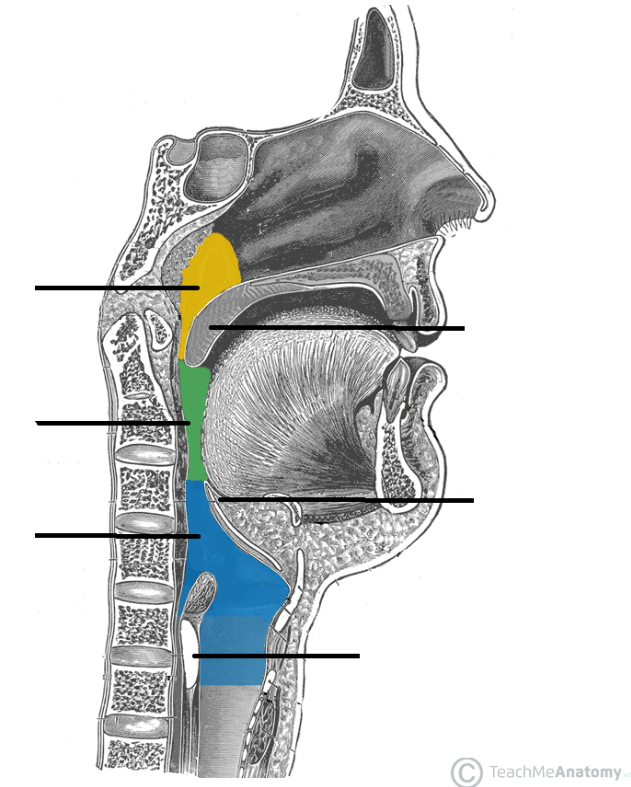

Nasopharynx

yellow highlight

Oropharynx

green highlight

Laryngopharynx

blue highlight